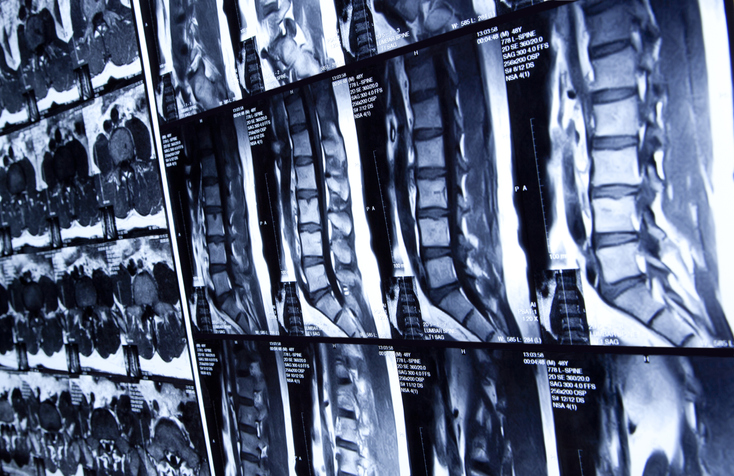

A prospective, randomized, controlled, single-blind, multicenter, pivotal trial that will evaluate the safety and effectiveness of Adherus dural sealant when used in conjunction with standard methods of dural repair in spinal procedures. This trial uses the commercially available DuraSeal Exact (P080013b) as an active control. The trial is designed to demonstrate non-inferiority of Adherus dural sealant to DuraSeal Exact. Study participants will be followed at discharge or between postoperative days 1 through 4 from the index procedure (whichever occurs first) and at 30 days and 90 days post-index procedure.

- Scheduled for an elective spinal procedure that will require a planned durotomy